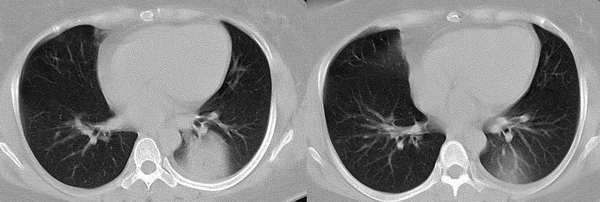

以下是引用wawaquan在2006-2-4 13:32:00的发言:[br]双上叶后段及右下叶多发大小不等圆形高密度影,与血管影相连;左下叶背段呈软组织密度影,边缘膨突,其内见一点状气体密度影,邻近胸膜增厚;纵隔淋巴结不大。[br] 女性,32岁,正哺乳期。近一周发热咳嗽,今晨咳血一次。 [br] 考虑:①双上叶后段及右下叶多发转移瘤,建议查盆腔排除子宫滋养叶细胞肿瘤。[br]②左下叶背段阻塞性炎症可能大。